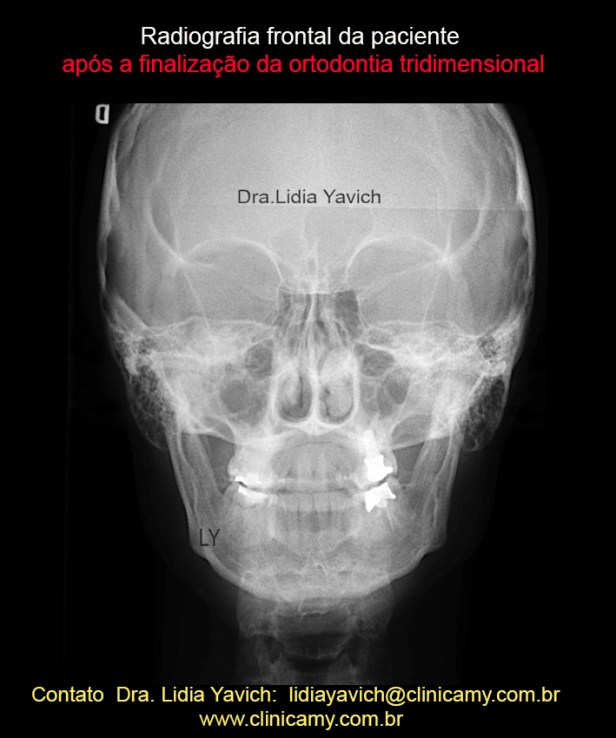

Radiografia frontal da paciente após a finalização da segunda fase do tratamento mediante uma ortodontia tridimensional e reabilitação neuromuscular fisiológica.

Radiografia frontal da paciente após a finalização da segunda fase do tratamento mediante uma ortodontia tridimensional e reabilitação neuromuscular fisiológica.